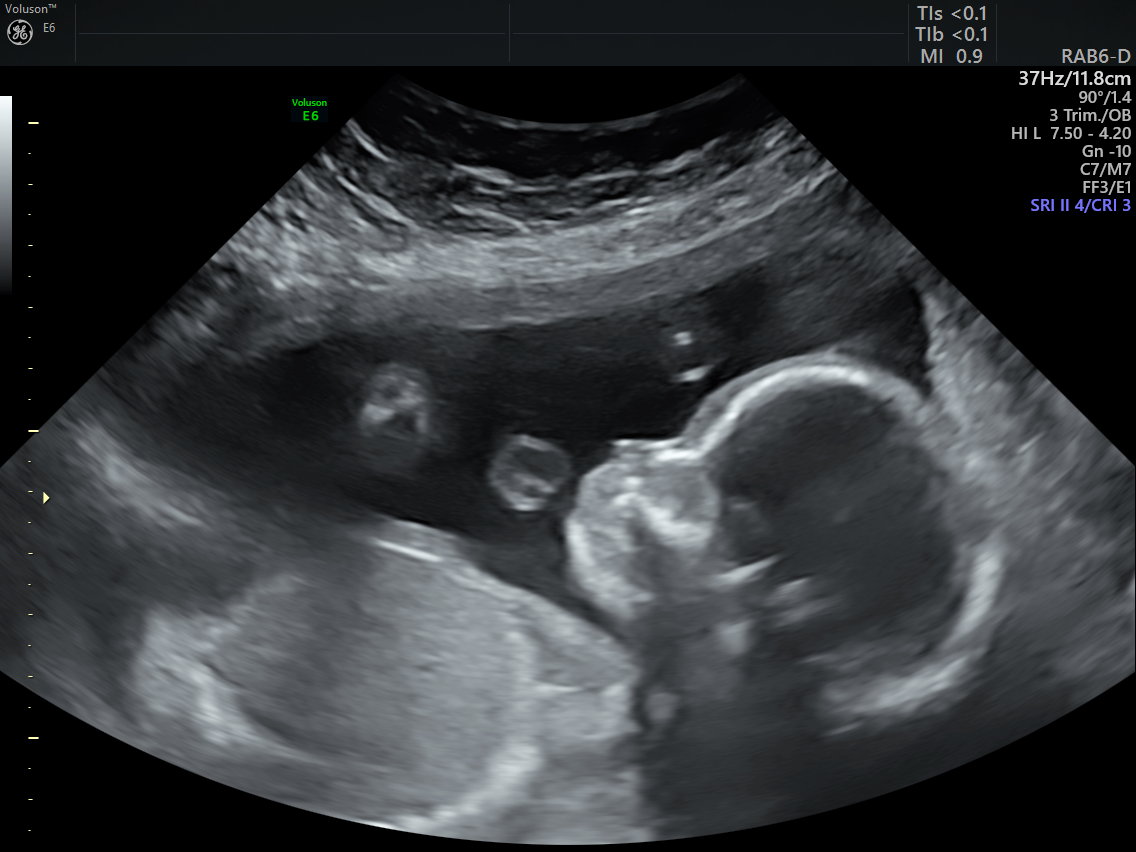

How Long Can A Twin Be Hidden In An Ultrasound . How early can you see twins on an ultrasound? A later ultrasound might reveal there actually is another. A twin may go undetected when an ultrasound is performed before the 8 th week of pregnancy. Very well family explains that 2d ultrasounds catch a glimpse of one twin because the other is shadowed from view. Most patients have their first ultrasound to confirm gestational dating between six and thirteen weeks. In some cases, healthcare providers may be able to identify the presence of twins even earlier, especially with advanced ultrasound technology. When your doctor looks at your ultrasound, he is essentially looking at an image of your womb, explained verywell family, but in. During the early stages of pregnancy, an ultrasound may reveal a hidden twin. What usually happens when a twin is hidden, according to verywell family, is that early ultrasounds might visualize only one embryo. The likelihood of having a hidden twin varies depending on several factors, including the type of pregnancy (singleton, fraternal twins, or. The doctor should be able to confirm multiples at this time. This occurs when one twin is positioned behind the other, making it difficult to detect. 2d ultrasounds are less accurate because the fetal poles and yolk sacs are not developed fully. Twins can typically be detected on ultrasound during the first trimester, usually around 6 to 8 weeks of gestation. When do twins show up on ultrasound?

In some cases, healthcare providers may be able to identify the presence of twins even earlier, especially with advanced ultrasound technology. Most patients have their first ultrasound to confirm gestational dating between six and thirteen weeks. The earliest you can typically expect to see twin fetuses on an ultrasound is around six weeks. A later ultrasound might reveal there actually is another. During the early stages of pregnancy, an ultrasound may reveal a hidden twin. When your doctor looks at your ultrasound, he is essentially looking at an image of your womb, explained verywell family, but in. This occurs when one twin is positioned behind the other, making it difficult to detect. Twins can typically be detected on ultrasound during the first trimester, usually around 6 to 8 weeks of gestation. 2d ultrasounds are less accurate because the fetal poles and yolk sacs are not developed fully. The doctor should be able to confirm multiples at this time.

How Long Can A Twin Be Hidden In An Ultrasound The earliest you can typically expect to see twin fetuses on an ultrasound is around six weeks. Very well family explains that 2d ultrasounds catch a glimpse of one twin because the other is shadowed from view. During the early stages of pregnancy, an ultrasound may reveal a hidden twin. 2d ultrasounds are less accurate because the fetal poles and yolk sacs are not developed fully. The earliest you can typically expect to see twin fetuses on an ultrasound is around six weeks. A later ultrasound might reveal there actually is another. A twin may go undetected when an ultrasound is performed before the 8 th week of pregnancy. The likelihood of having a hidden twin varies depending on several factors, including the type of pregnancy (singleton, fraternal twins, or. Twins can typically be detected on ultrasound during the first trimester, usually around 6 to 8 weeks of gestation. What usually happens when a twin is hidden, according to verywell family, is that early ultrasounds might visualize only one embryo. When do twins show up on ultrasound? How early can you see twins on an ultrasound? Most patients have their first ultrasound to confirm gestational dating between six and thirteen weeks. When your doctor looks at your ultrasound, he is essentially looking at an image of your womb, explained verywell family, but in. In some cases, healthcare providers may be able to identify the presence of twins even earlier, especially with advanced ultrasound technology. The doctor should be able to confirm multiples at this time.